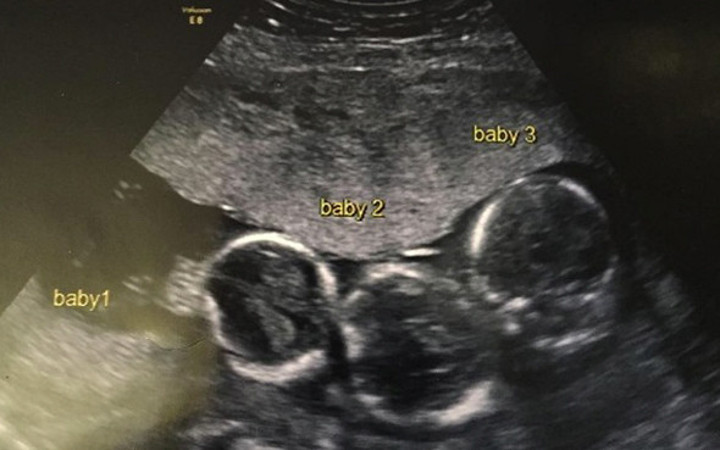

İNGİLTERE'nin Liverpool şehrinde yaşayan Indiana isimli bir kız çocuğu sahibi Becki-Jo Allen ve Liam Tierney çifti, milyonda bir gerçekleşen olayın konusu oldular. oktorlar 23 yaşındaki Becki-Jo Allen’a müjdeli haberi verdiğinde kadın şaşırdı kaldı. Beck-Jo doğum esnasında bir başka sürprizle daha karşılaştı. Meğerse çocuklar tek yumurta üçüzüymüş. Bunun gerçekleşme ihtimali 200 milyonda birmiş. Peki hikaye burada bitti mi sandınız? Hayır hikayenin geri kalanı büyük bir sürpriz.

Aile kızlarına kardeş istiyordu ancak üçüzleri olacağını tahmin edemediler. Hamileliğinin ilk haftalarında Becki-Jo hastalandı ve başı ağrımaya başladı. Ultrasona girince üçüzleri olacağını öğrendi. Becki-Jo, Liverpool Echo’ya “Hayatımın en büyük sürpriziydi! Sülalemizde üçüzleri olan kimse yok. Haliyle çok şaşırdık” dedi. Hamileliğinin 31. haftasında Becki-Jo sezaryenle Roman, Rocco ve Rohan’ı dünyaya getirdi. Bebeklerin her biri 1.5 kiloydu ve altı haftalarını yoğun bakımda geçirdiler.